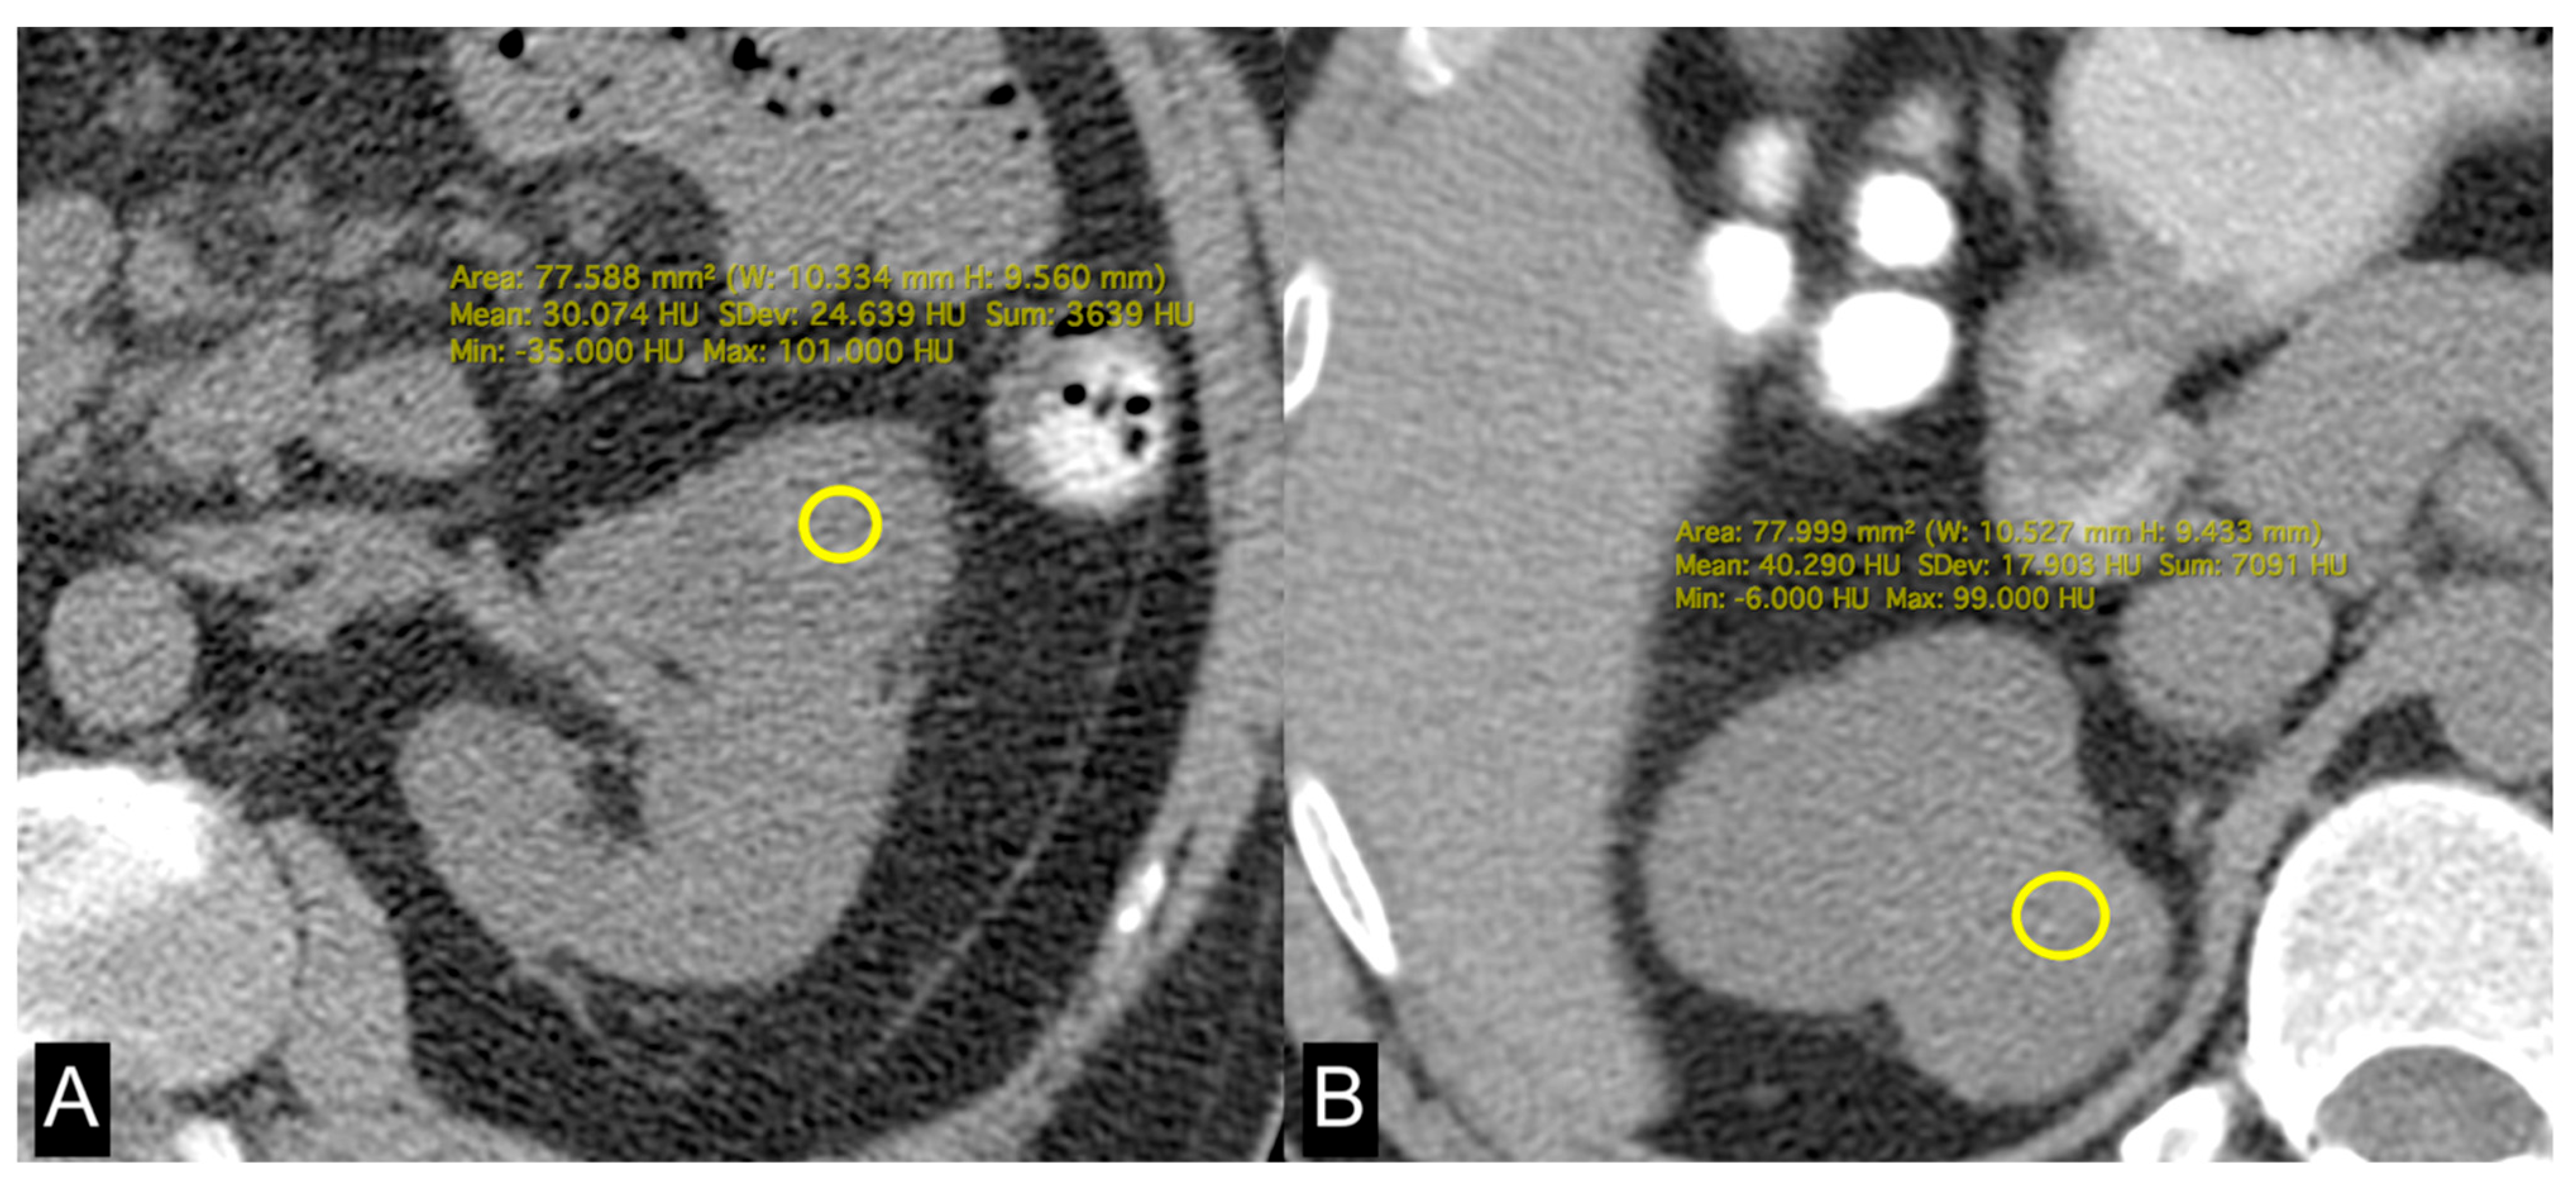

| HU | 34 (27, 37) | 36 (32, 42) | 0.021 |

| VAT (cm2) | 273 (225, 343) | 159 (95, 240) | 0.003 |

| HU | 30 (24, 32) | 37 (33, 40) | 0.002 |